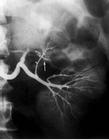

表浅血管瘤或脉管畸形的诊断并不困难。位置较深的血管瘤或脉管畸形应行体位移动试验和靠穿刺来确定。对动静脉畸形以及深层组织内的静脉畸形、大囊性淋巴管畸形等,为了确定其部位、大小、范围及其吻合支的情况,可以采用超声、动脉造影、瘤腔造影或磁共振血管成象(MRI或MRA)来协助诊断(方法详见《口腔颌面X线诊断学》及有关参考书籍),并为治疗作参考。从细胞生物学分类的观点来看,成人的脉管病损基本上都应属脉管畸形。婴幼儿期的动静脉畸形、微静脉畸形、淋巴管畸形亦均属脉管畸形。高出皮肤的所谓杨梅样血管瘤自发性消退的可能性较大,一般应属血管瘤。婴幼儿期特别是一出生即发现的静脉畸形,其所属类型如何判断尚需进一步研究。有研究指出:血清中血管内皮生长因子(VEGF)和雌激素受体等在血管瘤明显升高;而细胞凋亡基因bcl-2在脉管畸形中呈高表达,但仅供参考。

动静脉畸形,主要采用手术治疗。手术时应先结扎切断与肿瘤交通的动脉,尔后再切除病变。有时因病变广泛,手术时需作一侧或双侧颈外动脉结扎,以减少出血。近年来,由于介入放射学(interventional radiology)的发展可以应用经导管动脉栓塞技术(transcather arterial embolization, TAE, TCAE),以控制和减少术中出血。其止血效果远较颈外动脉结扎为好;因为除动脉主干外,动脉的各级分支,直至终末支均可得到栓塞,没有末梢血管压力骤降、管腔开放、反而形成侧支循环之弊。常用的有效而安全的栓塞材料是明胶海绵。应当指出:曾有人试图单独应用颈外动脉结扎术以治疗动静脉畸形,经验和实验研究证明,不但无效,而且可以促进非正规的侧支循环形成,反给后期进一步治疗带来困难和麻烦。应用颈外动脉结扎术治疗动静脉畸形不但在实际上是无效的,而且在理论上也是错误的。颌骨中心性血管畸形手术时极易出血,除准备足够血源外,为控制出血可采用低温、降压麻醉。手术时应结扎一侧或双侧颈外动脉,或直接先结扎下牙槽动脉(或上颌动脉);当然,TAE技术比颈外动脉结扎能更有效地控制术中出血。以前对颌骨中心性血管畸形多采用切骨手术,目前则倾向于尽量采用保存性手术;其中介入性治疗已初步取得成功,宜作为首选。其次,可选择在有效的控制出血后,仅刮除骨内病损,能保留更多的骨组织以维护面部外形。当然对于骨质破坏过多过大,出血难以完全控制的病例也可采用切骨术。淋巴管畸形的治疗主要采用手术,特别是对微囊型患者。小的病损可以全部切除;大的病损也可采用分期切除,或为改善功能和容貌的部份切除术。平阳霉素治疗